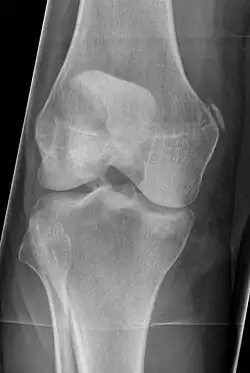

Diagnosis is typically made on radiographs demonstrating the Pellegrini-Stieda syndrome sign accompanied by pain or restriction of range-of-motion of the knee joint.[2] Pellegrini-Stieda syndrome sign is typically described by a longitudinally linear opacity, which is a process that is describes characteristic of calcification in the soft tissue located medial to the medial femoral condyle.[2] This calcification seen on imaging represents the ossification of the medial collateral ligament, which typically does not develop until approximately three weeks after the initial injury.[2]It is important to note to distinguish this radiographic finding from that of a medial femoral condyle avulsion fracture, which is an injury in which a pulling force of a tendon or ligament fractures away a piece of the bone from its attachment site.[2]

The Pellegrini-Stieda syndrome is a relatively infrequent phenomenon and is commonly associated with sporting injuries. Pellegrini-Stieda Syndrome Is more frequent in the males between 25 and 40 years of age. Direct trauma or in a distant site (skull or spine), repetitive trauma, or after an overstretching injury to the medial collateral ligament and joint capsule can result in an avulsion of the medial femoral condyle or a tear of ligaments, tendons. Ossification could happen within 11 days to 6 weeks after post trauma. A network of the new bone formation around the periphery of the mass of the medial condyle is formed in 6 to 8 weeks. Duration of the condition is usually about 5 to 6 months.[4]

After a while, the phenomena could occur: the inflammation subsides with partial or complete resorption of the calcium salts, or the mass becomes ossified and may be connected by a pedicle to the femoral condyle.[4]